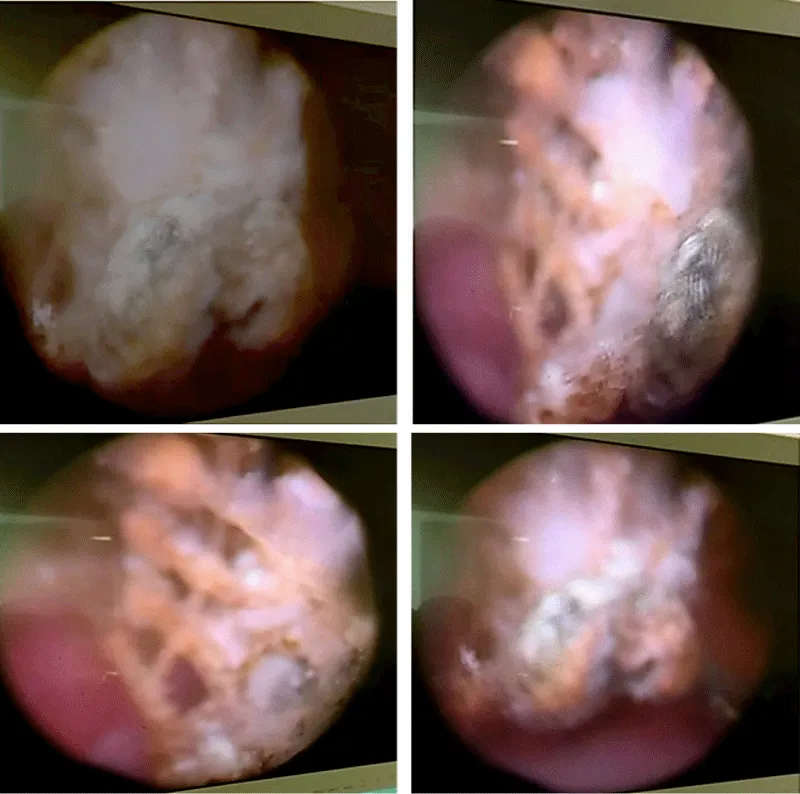

Initial evaluation included urinalysis and bladder ultrasound. Ultrasound demonstrated an intravesical calculus without upper urinary tract dilatation. Given the history of prior mesh-based prolapse repair and the presence of a bladder stone, diagnostic cystoscopy was performed to identify a potential intravesical foreign body. Cystoscopy revealed a vesical calculus adherent to exposed mesh fibers protruding into the bladder lumen, confirming intravesical erosion of the promontofixation mesh (Figure 1). The surrounding bladder mucosa appeared inflamed at the contact site.

Figure 1: Cystoscopic view showing a bladder stone formed on exposed intravesical mesh fibers.